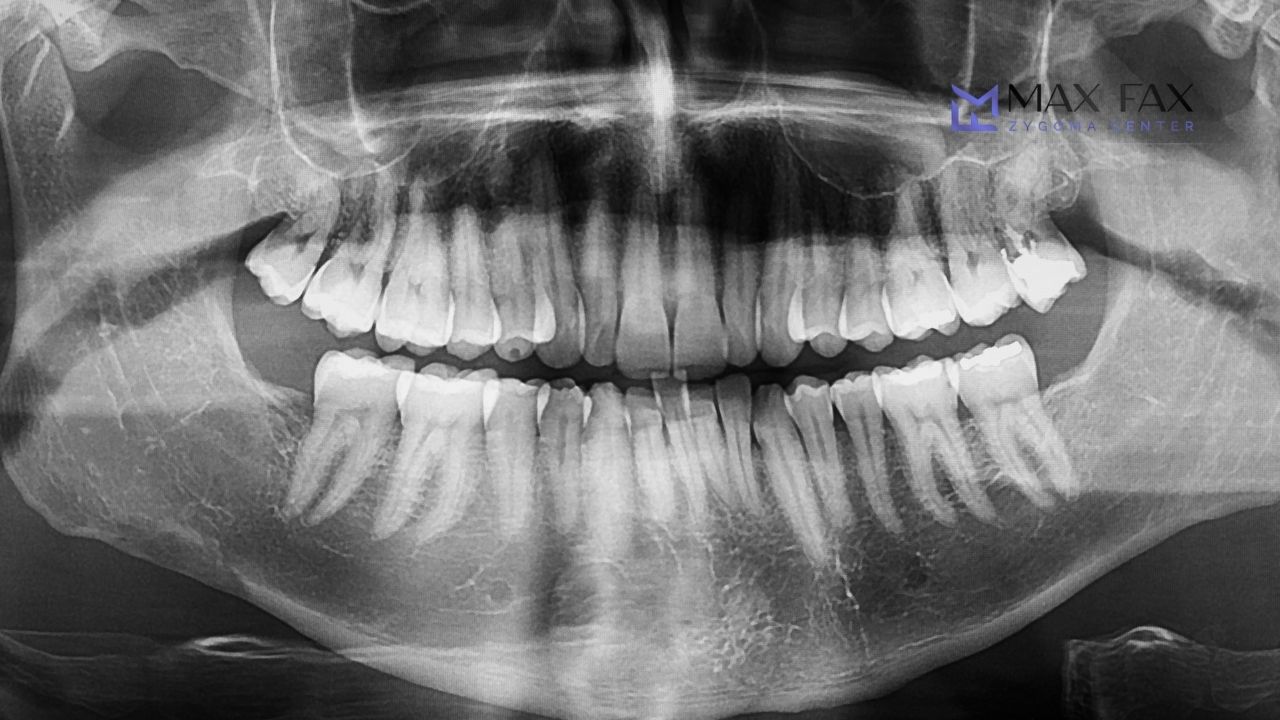

Under the care of Prof. Dr. Celal Çandırlı, each case is evaluated individually using 3D imaging, digital planning and clinical expertise. Depending on your anatomy and treatment goals, your plan may include one or more of the following approaches.

We assess your dental history, medical background, goals and expectations. High-resolution 3D imaging is performed to evaluate bone quality and anatomical structures.